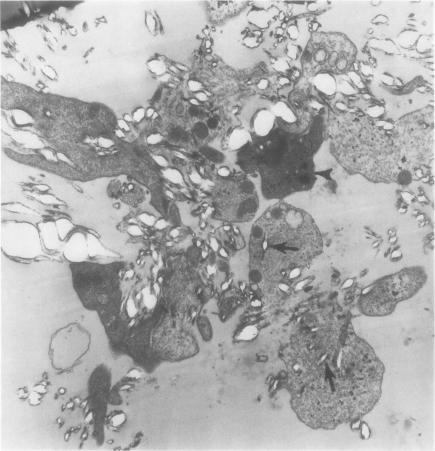

The release of human platelet constituents by the etiologic agent of gout, the monosodium urate crystal, is described here. In suspensions of washed platelets, response to urate crystals proceeded in two phases: A secretory phase involved the rapid active release of serotonin, ATP, and ADP with little loss of lactic dehydrogenase or beta-glucuronidase. A lytic phase involved the slower loss of all platelet constituents. Both phases were inhibited by iodoacetate plus dinitrophenol, suggesting an energy requirement. In ultrastructural studies, lysis of washed platelets which appeared to contain crystals was seen. Urate crystals were also shown to induce serotonin release and platelet lysis in citrated platelet-rich plasma. Since urate crystals are deposited at a variety of sites, urate crystal-platelet interaction in vivo is a possibility. Such interactions, leading to release of platelet constituents, might contribute to gouty inflammation or to enhanced atherogenesis.

本文描述了痛风的病原体尿酸钠晶体导致人血小板成分的释放。在洗涤过的血小板悬液中,对尿酸盐晶体的反应分两个阶段进行:分泌阶段涉及5-羟色胺、三磷酸腺苷(ATP)和二磷酸腺苷(ADP)的快速主动释放,而乳酸脱氢酶或β-葡萄糖醛酸酶几乎没有损失。溶解阶段涉及所有血小板成分的较慢损失。两个阶段均受到碘乙酸盐加二硝基苯酚的抑制,提示需要能量。在超微结构研究中,可见似乎含有晶体的洗涤过的血小板发生溶解。尿酸盐晶体还显示可在枸橼酸化的富含血小板血浆中诱导5-羟色胺释放和血小板溶解。由于尿酸盐晶体沉积在多种部位,因此尿酸盐晶体与血小板在体内发生相互作用是有可能的。这种导致血小板成分释放的相互作用可能会导致痛风性炎症或增强动脉粥样硬化的发生。